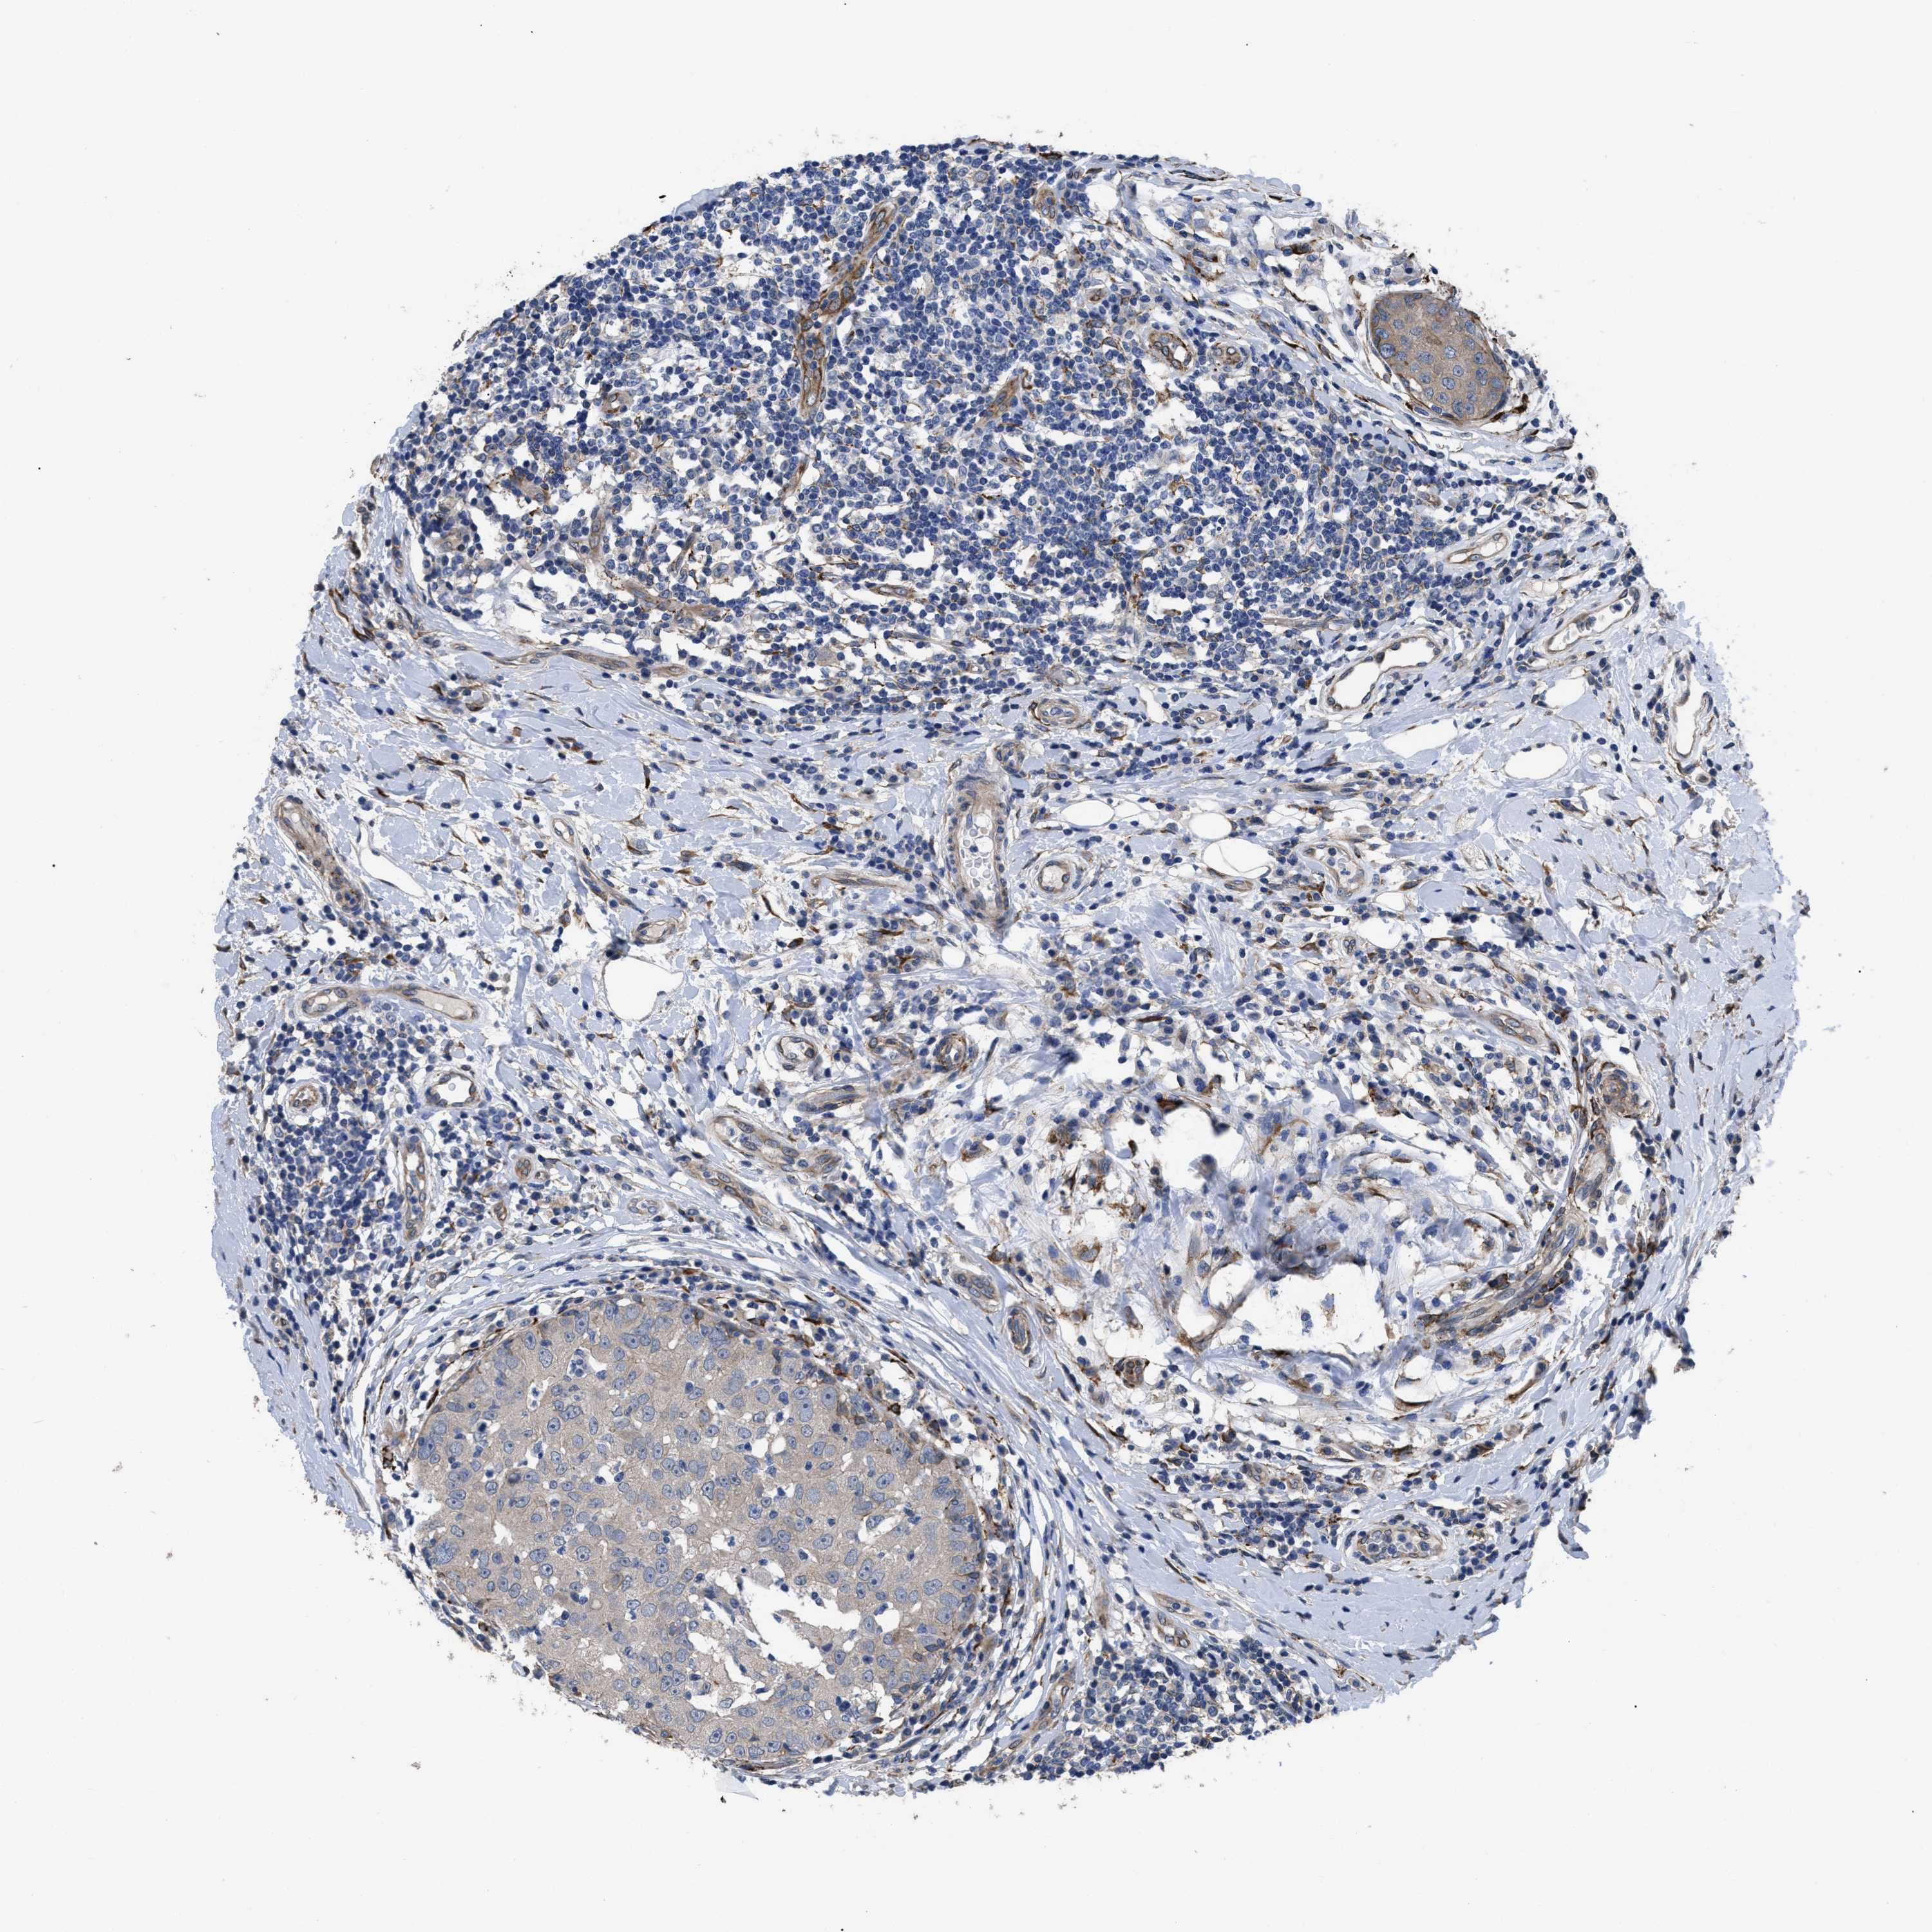

CANCER BREAST CANCER Show tissue menu

BRCA TCGA BRCA VALIDATION PROTEIN EXPRESSION

Breast cancer

Human cancer